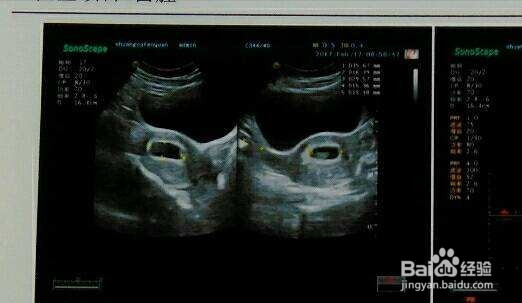

3、怀孕12周以内应该保证做一次妇科B超,来确定孕周,推算预产期。